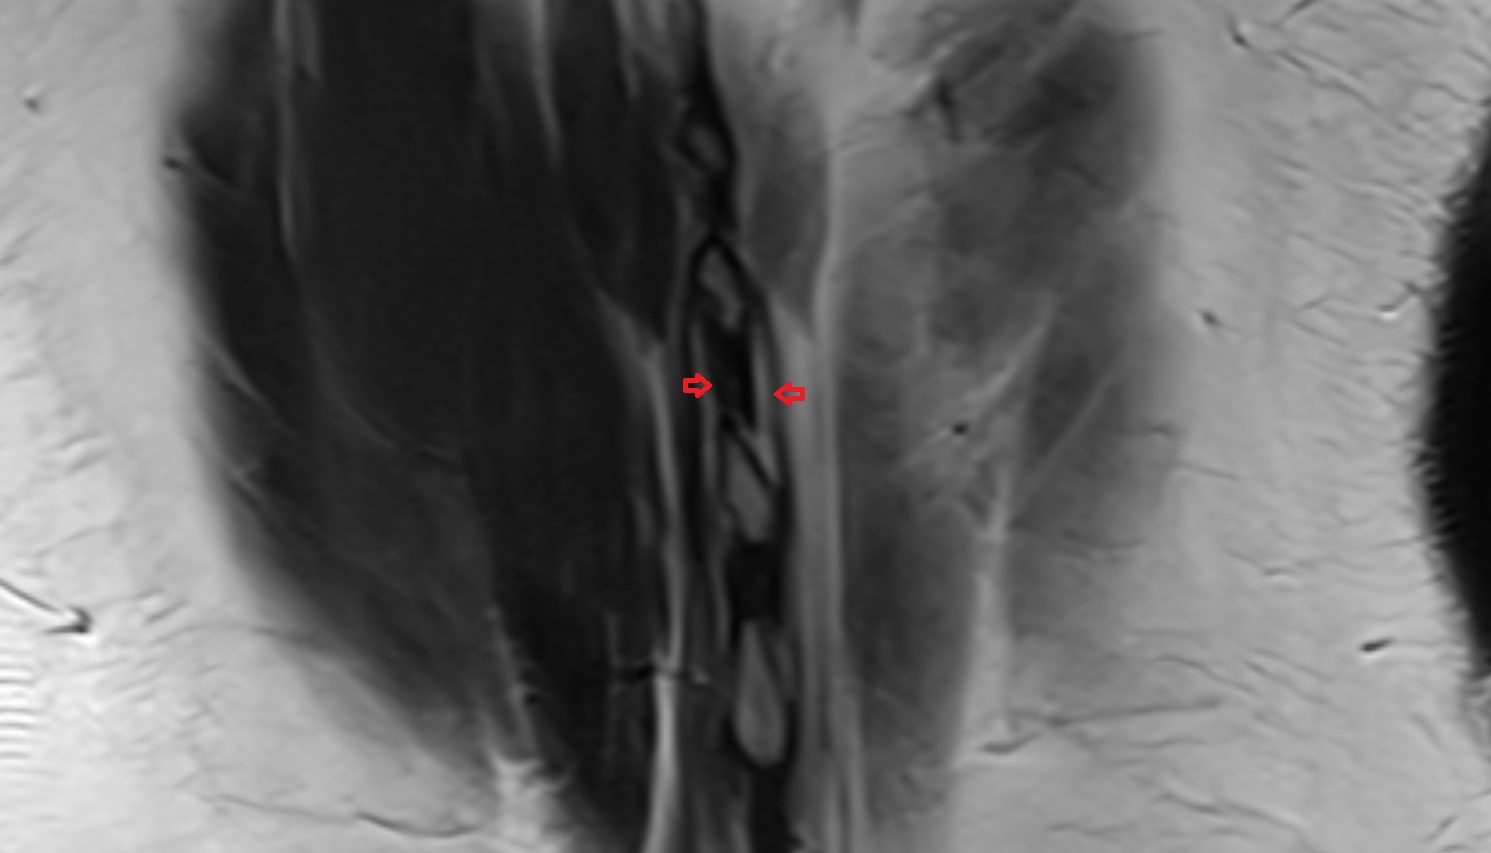

- Traversing nerve root of spinal nerve

- Exiting nerve root of spinal nerve

- Dorsal traversing nerve root

- Ventral traversing nerve root

- Dorsal exiting nerve root

- Ventral exiting nerve root

- Dorsal root ganglion of spinal nerve